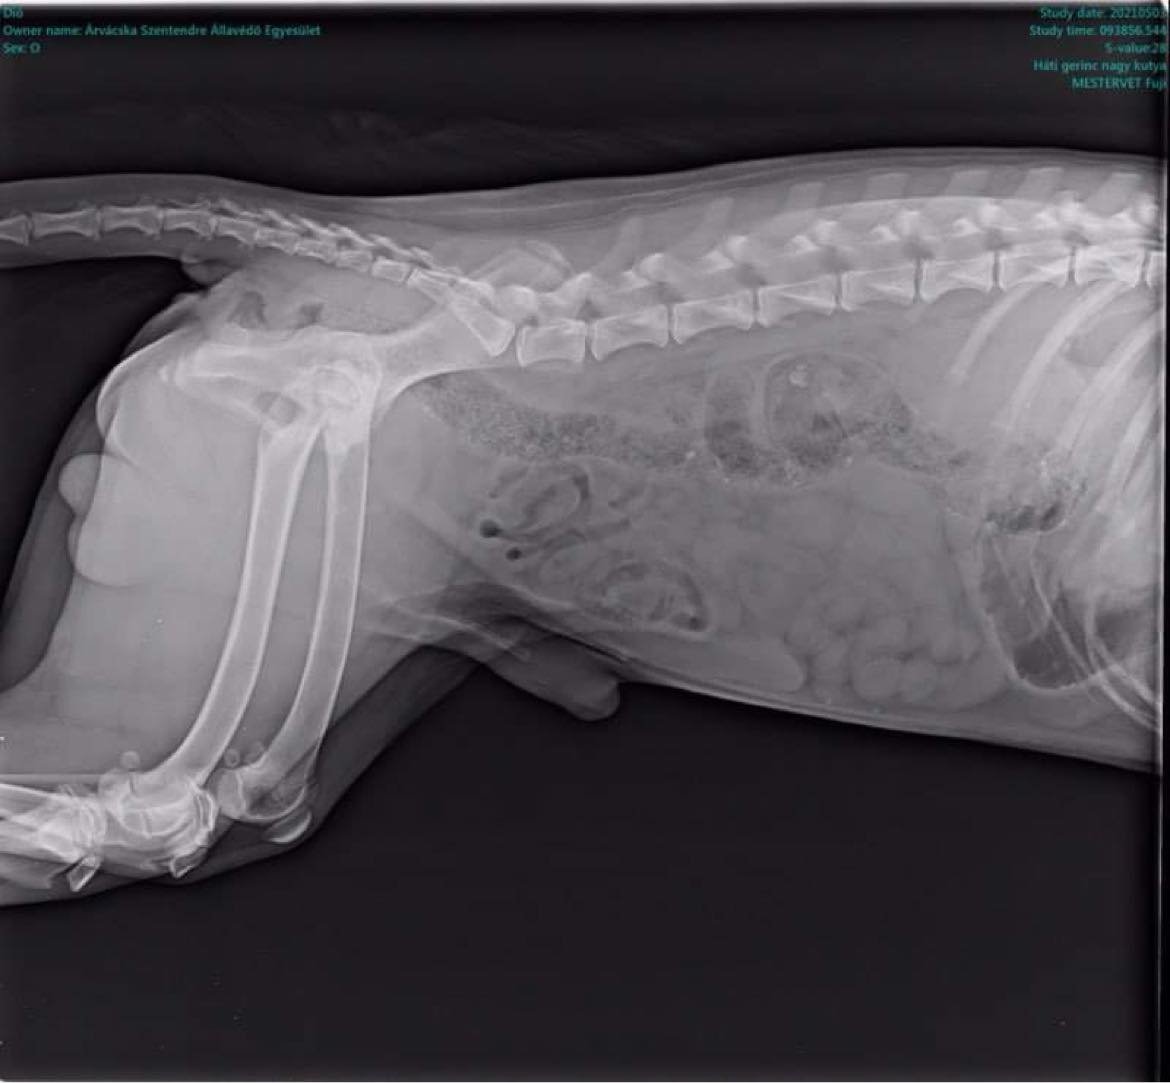

Tegnapi nap tudtunk meg, hogy Dió kutyusunkat meg kell műteni, mert combnyaktörése volt, és a fájdalommentes élethez minél előbb segítségre van szüksége.